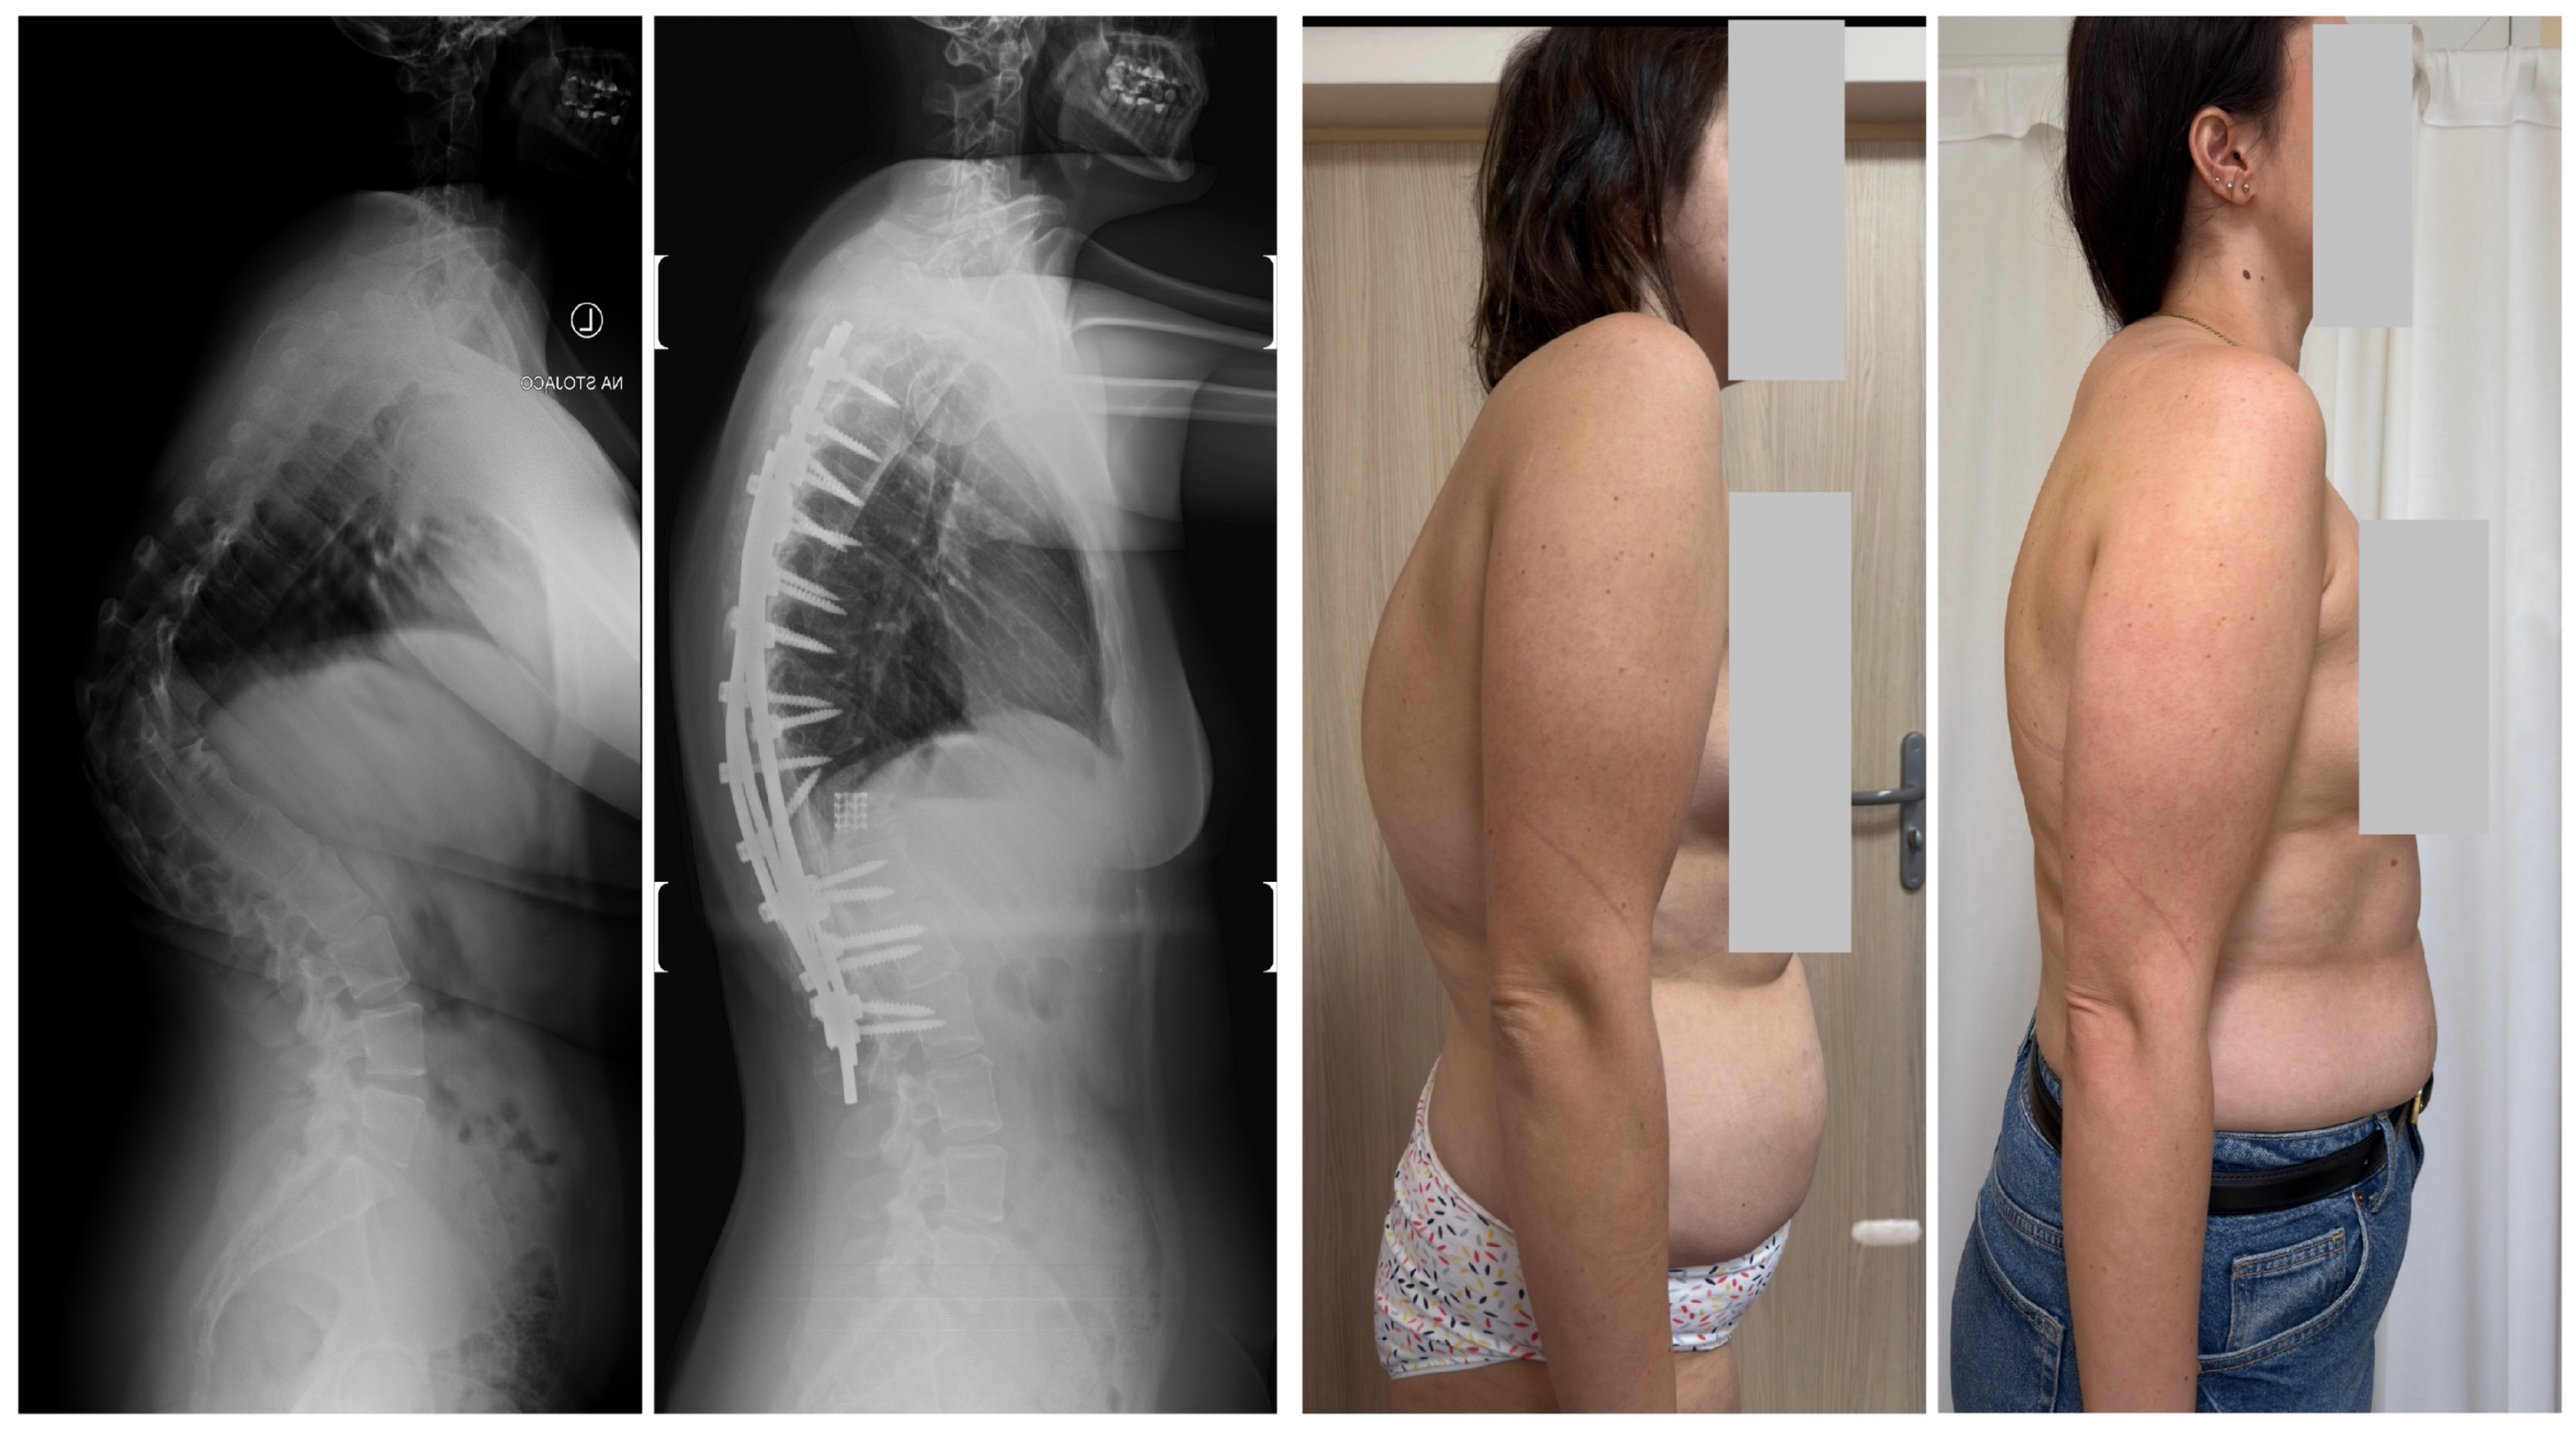

- Grabala, P.; Fani, N.; Gregorczyk, J.; Grabala, M. Posterior-only T11 vertebral column resection for pediatric congenital kyphosis surgical correction. Medicina 2024, 60, 897. [Google Scholar] [CrossRef] [PubMed]